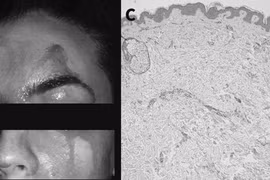

Răng mọc trong hốc mũi

(GLO)- Bé N.Đ.D. (4 tuổi, trú tại Yên Dũng, Bắc Giang) được gia đình đưa vào Bệnh viện Sản Nhi Bắc Giang khám vì trẻ thường xuyên chảy máu cam. Kết quả xác định, bé thường xuyên chảy máu cam do răng mọc ngược lên sàn mũi.